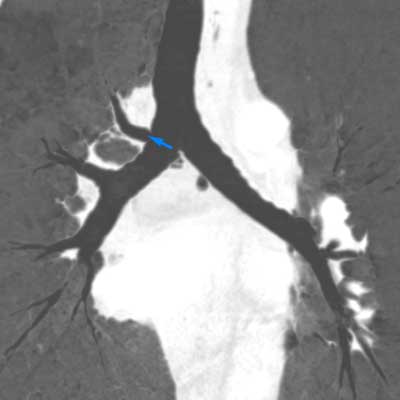

Figure 2

CECT of the thorax, lung window, coronal MinIP reconstruction. Tracheal bronchus arising at the right side of the carina (blue arrow).